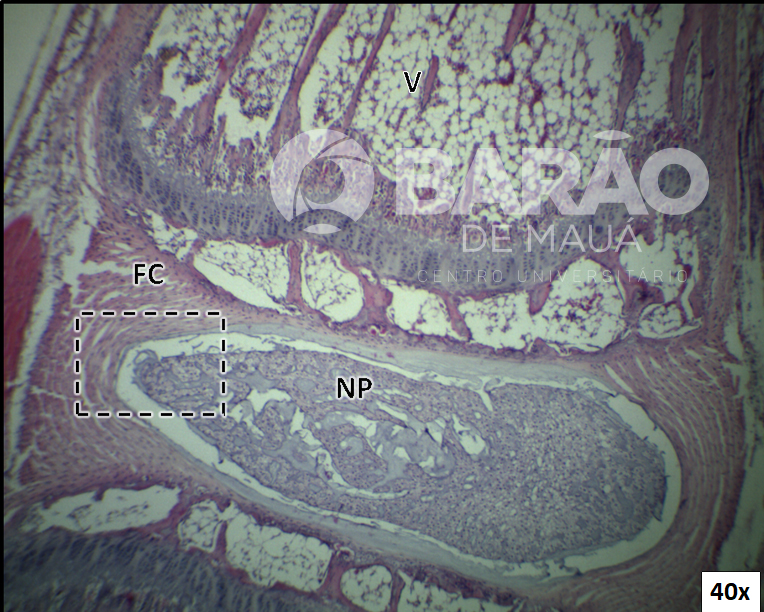

Cauda de Rato Disco Intervertebral - NP = núcleo pulposo, FC = fibrocartilagem e V = vértebra - Coloração: H&E

Cauda de Rato Disco Intervertebral - NP = núcleo pulposo, FC = fibrocartilagem e V = vértebra - Coloração: H&E.